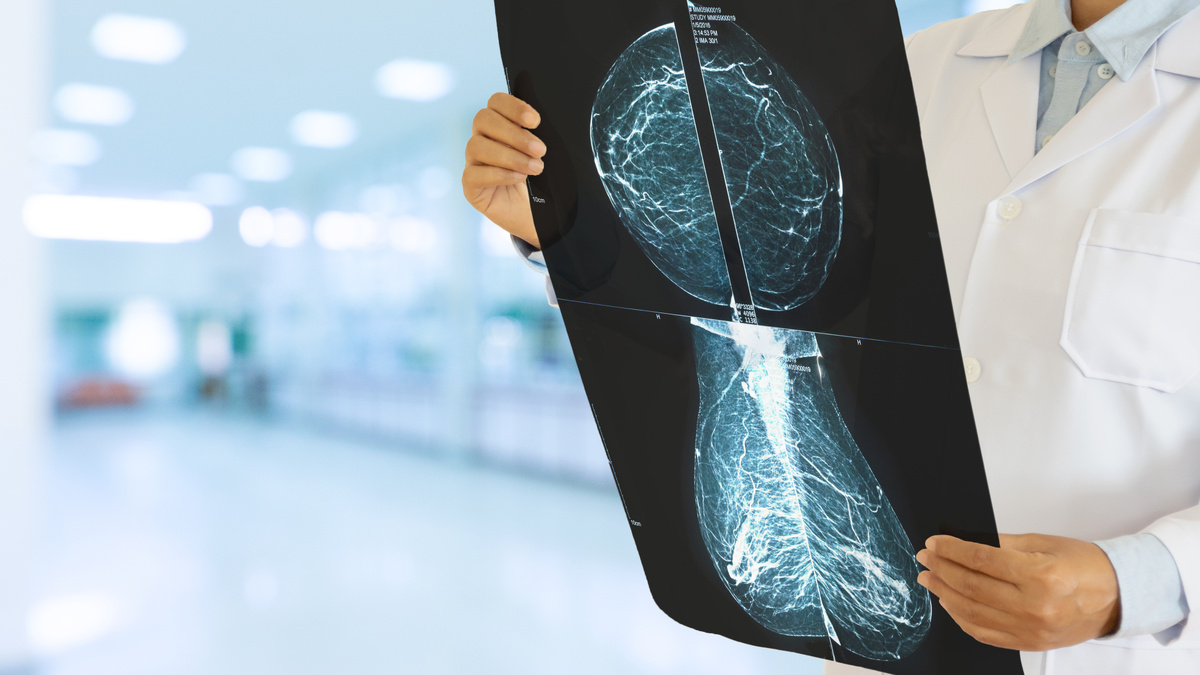

Кальцинаты молочной железы.

Потенциально злокачественные кальцинаты имеют ряд характерных признаков, отличающих их от доброкачественных образований:

• Размер: мелкие (до 0,5 мм)

• Контуры: нечеткие, неровные

• Форма: неправильная, могут быть линейными или разветвленными

• Распределение: кластерное (групповое), не менее 5 штук на кубический сантиметр

• Количество: большое

У доброкачественных кальцинатов тоже есть свои характерные признаки:

• Размер: крупные, хорошо визуализируются

• Контуры: ровные, четкие, часто округлые

• Форма: могут иметь характерный вид “яичной скорлупы”, “кофейной чашки”, “попкорна”

• Распределение: равномерное (диффузное).

• Количество: небольшое

• Особенности: часто связаны с воспалительными процессами, травмами, операциями

• Молочная железа. Кальцинаты в тканях железы часто обнаруживаются при профилактических обследованиях ( маммография, УЗИ). Их появление может быть связано с индивидуальными особенностями строения молочных желез, генетической предрасположенностью или перенесенными заболеваниями, а также онкологией. Необходимо учитывать признаки, о которых мы говорили выше.